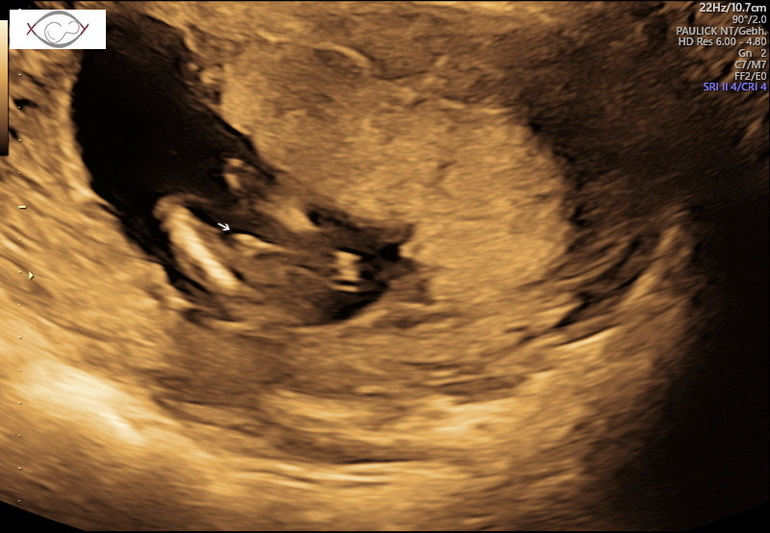

Ураааа!!!!! Мальчик!!! 😁😁😁🤗🤗🤗🥳🥳🥳

В 13н и 5д узистка предположила только, я сдавала нипт из за риска трисомии и заодно подтвердился пол 😁👍А на УЗИ мне вот стрелочкой указали, но всё же ещё не точно было.

Пол малыша) Определение пола на сроке 6-8 недель, по методу Рамзи